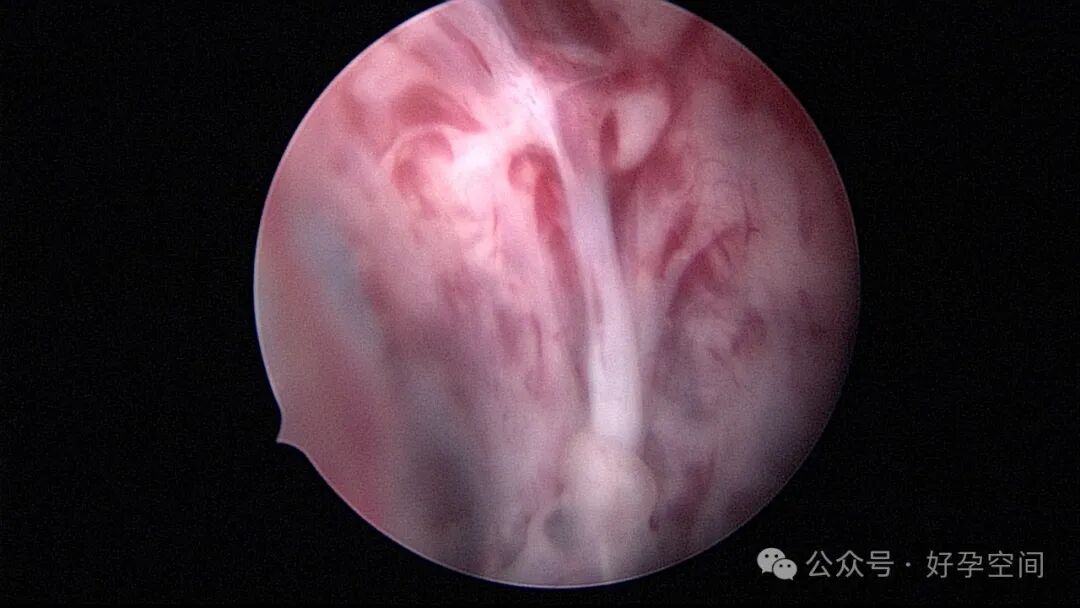

病例1:32岁,G8P3,剖宫产3次,本次停经50+天,计划外妊娠,宫腔镜辅助下清宫,见剖宫产瘢痕憩室,宫腔后壁2.5cm*2.0cm组织难以清除,宫腔镜电切送病检,病检结果为宫腔妊娠组织。